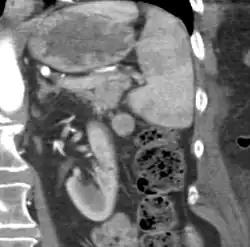

An accessory spleen is a small nodule of splenic tissue found apart from the main body of the spleen. Accessory spleens are found in approximately 10 percent of the population[1] and are typically around 1 centimeter in diameter. They may resemble a lymph node or a small spleen. They form either by the result of developmental anomalies or trauma.[2] They are medically significant in that they may result in interpretation errors in diagnostic imaging[2] or continued symptoms after therapeutic splenectomy.[1] Polysplenia is the presence of multiple accessory spleens rather than one normal spleen.

If splenectomy is performed for conditions in which blood cells are sequestered in the spleen, failure to remove accessory spleens may result in the failure of the condition to resolve.[1] During medical imaging, accessory spleens may be confused for enlarged lymph nodes or neoplastic growth in the tail of the pancreas,[5] gastrointestinal tract, adrenal glands or gonads.[2]